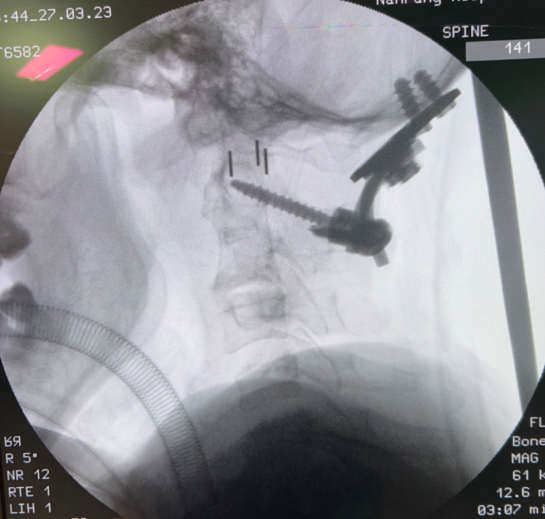

病例二:

簡介:

使用拱形枕骨板配合融合器進(jìn)行內(nèi)固定,術(shù)后隨訪效果良好。